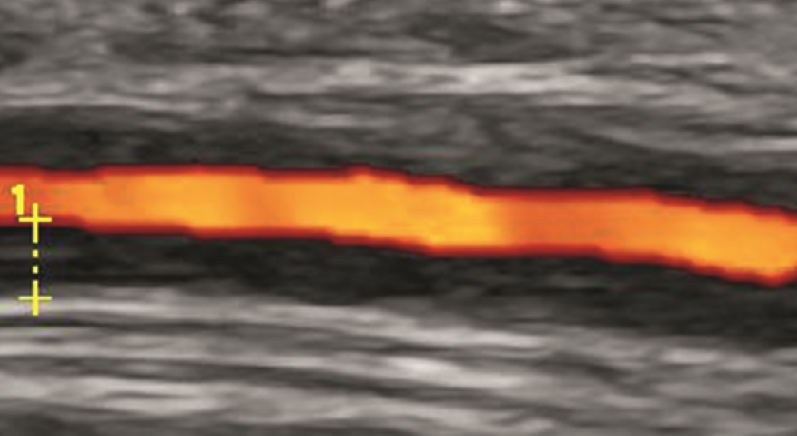

Zur Abklärung werden klinische Untersuchung, Blutwerte (CRP, BSG)) und bildgebende Verfahren wie Gefäßultraschall der Schläfenarterien (entzündliche Gefäßwandveränderung) eingesetzt; ergänzend kann ggf. auch eine Biopsie der Schläfenarterie erfolgen. Die Behandlung erfolgt in der Regel mit hochdosierten Kortikosteroiden, die später langsam reduziert und bei Bedarf durch weitere immunsuppressive Therapien ergänzt werden.​